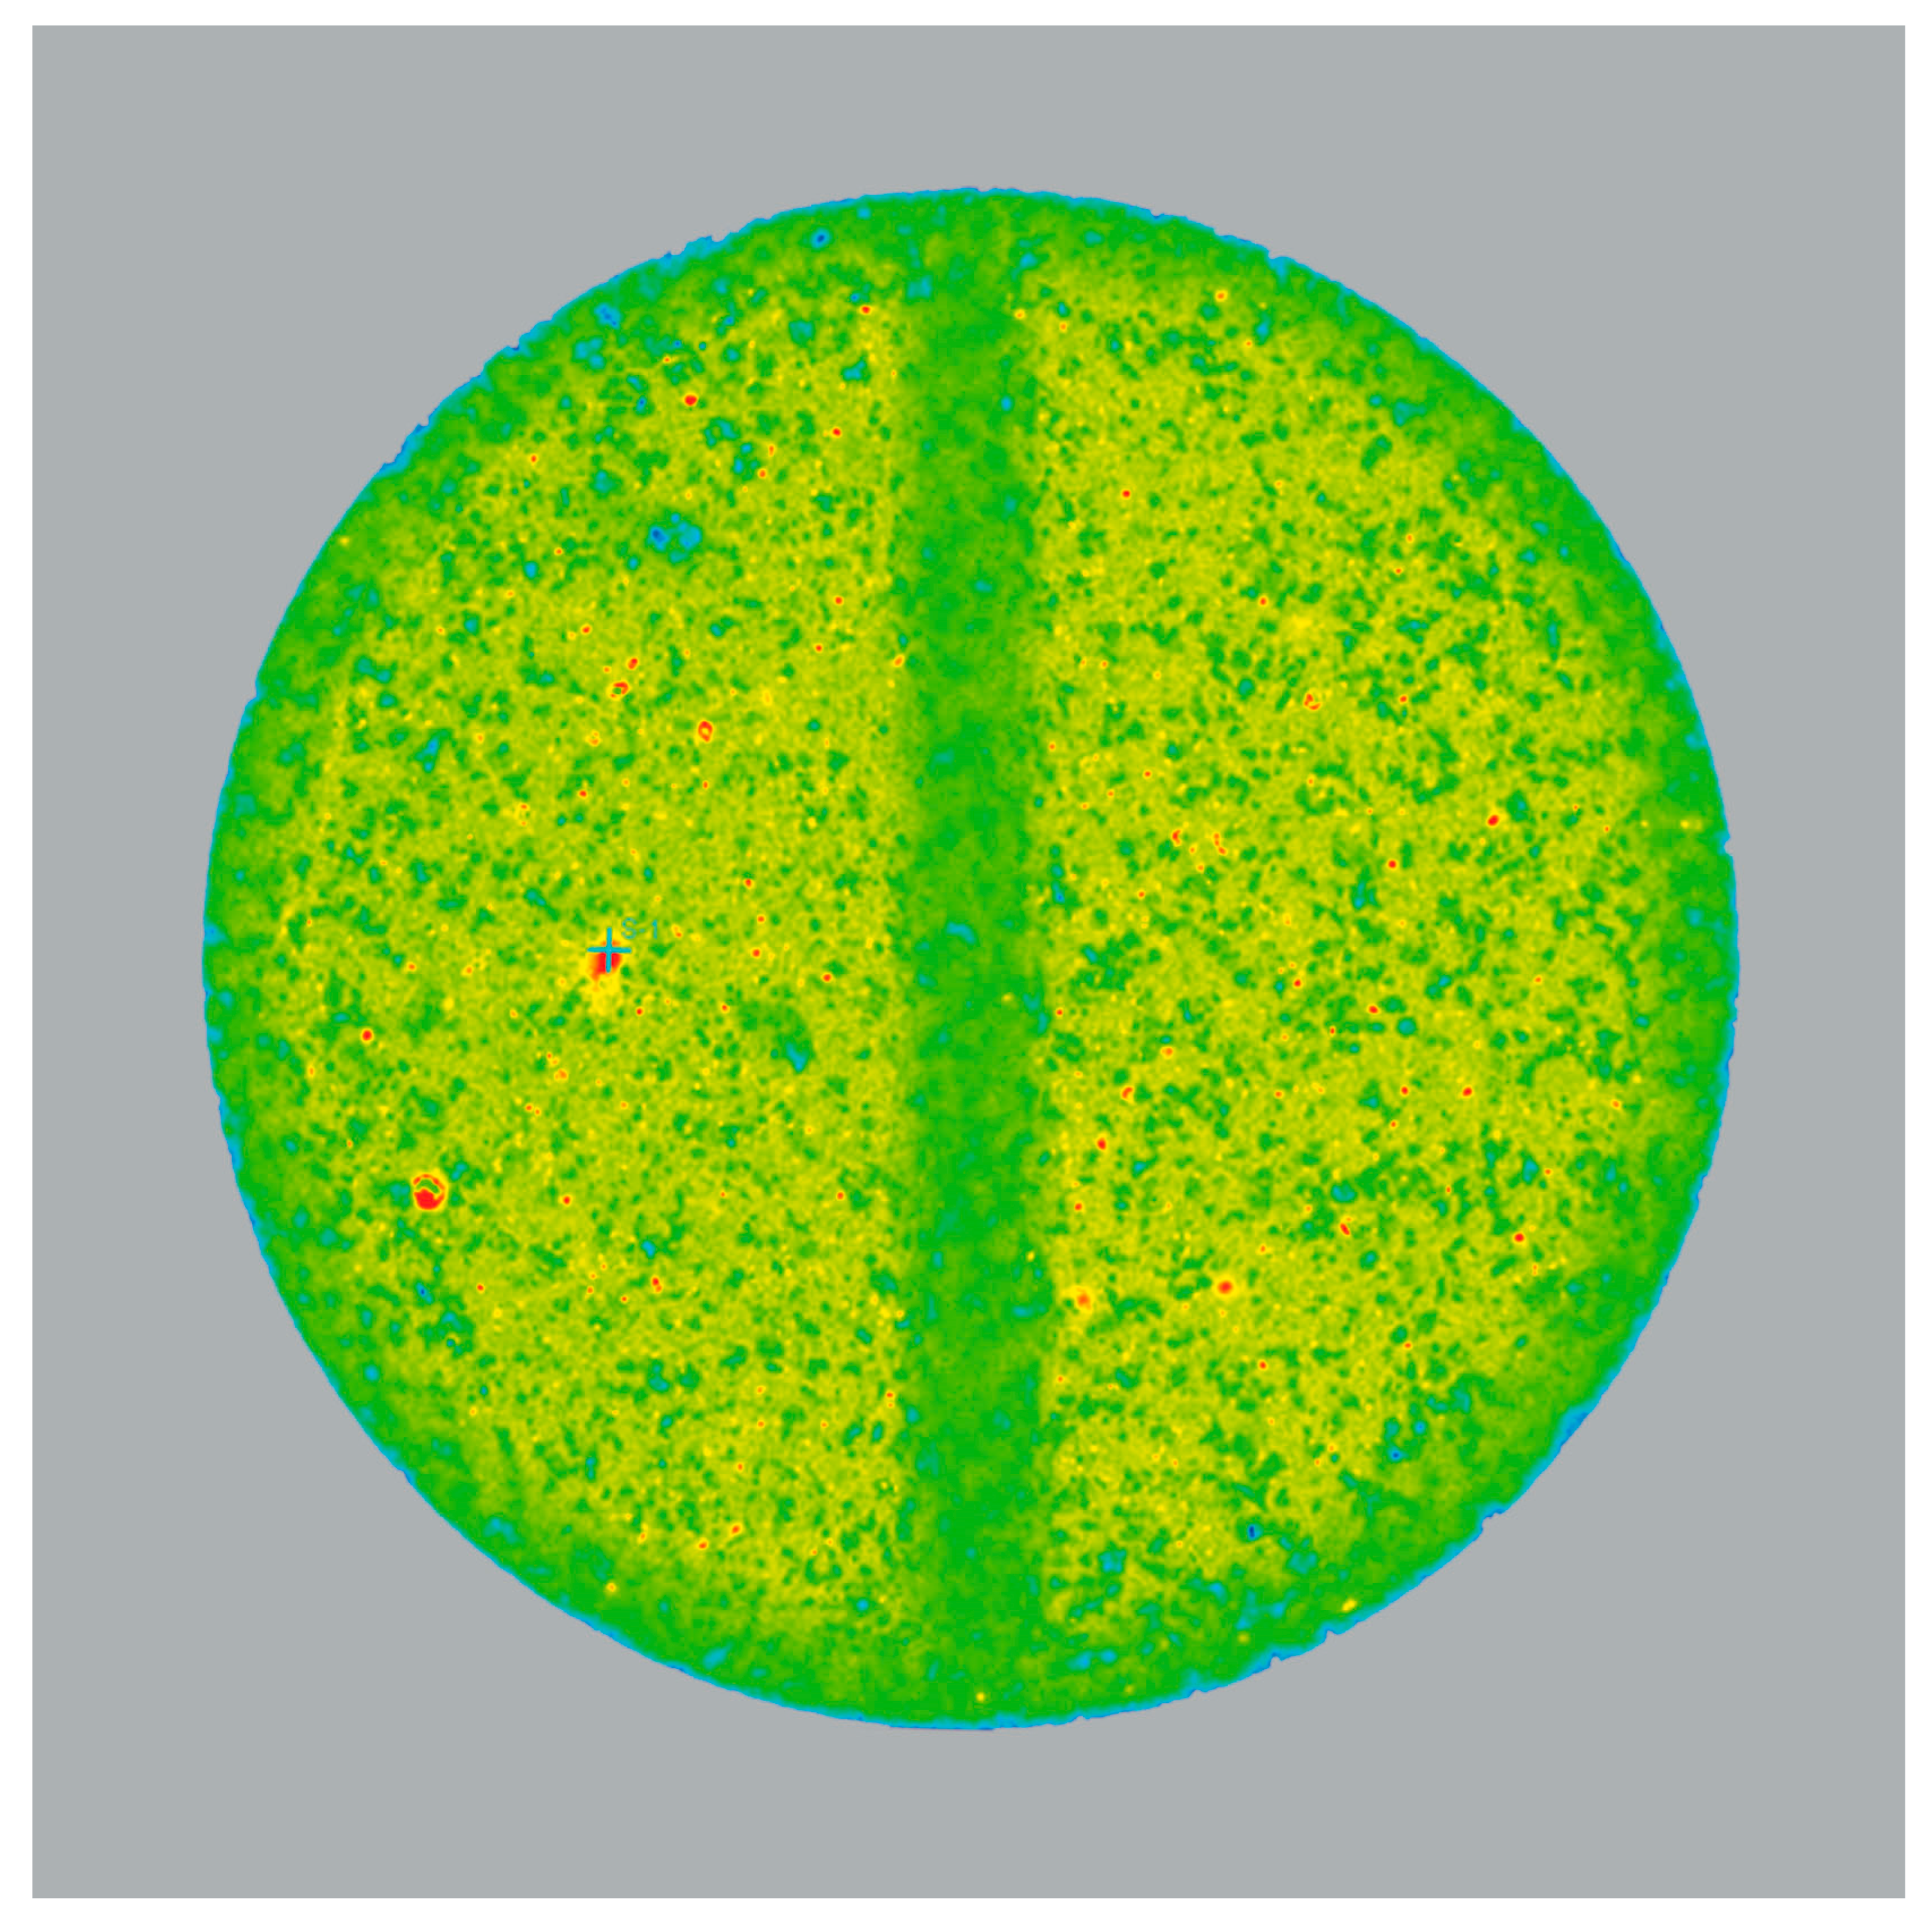

Figure 9 shows the Raman correlation map of the “Simethicone/Loperamide TSG” formulation. Red spots indicate areas of high correlation for Raman spectra with that of loperamide hydrochloride. Loperamide hydrochloride is distributed evenly in the tablet but variations in particle size are evident. This suggests the inhomogeneous particle size distribution of the drug substance. Larger crystals of loperamide hydrochloride were unable to break up in simethicone under the conditions of the process before being deposited on the carrier particles.

Figure 9.

Raman correlation map showing the spatial distribution of loperamide hydrochloride; red sites are those with the highest, and blue sites are those with the lowest correlation of the Raman spectrum with that of loperamide hydrochloride.